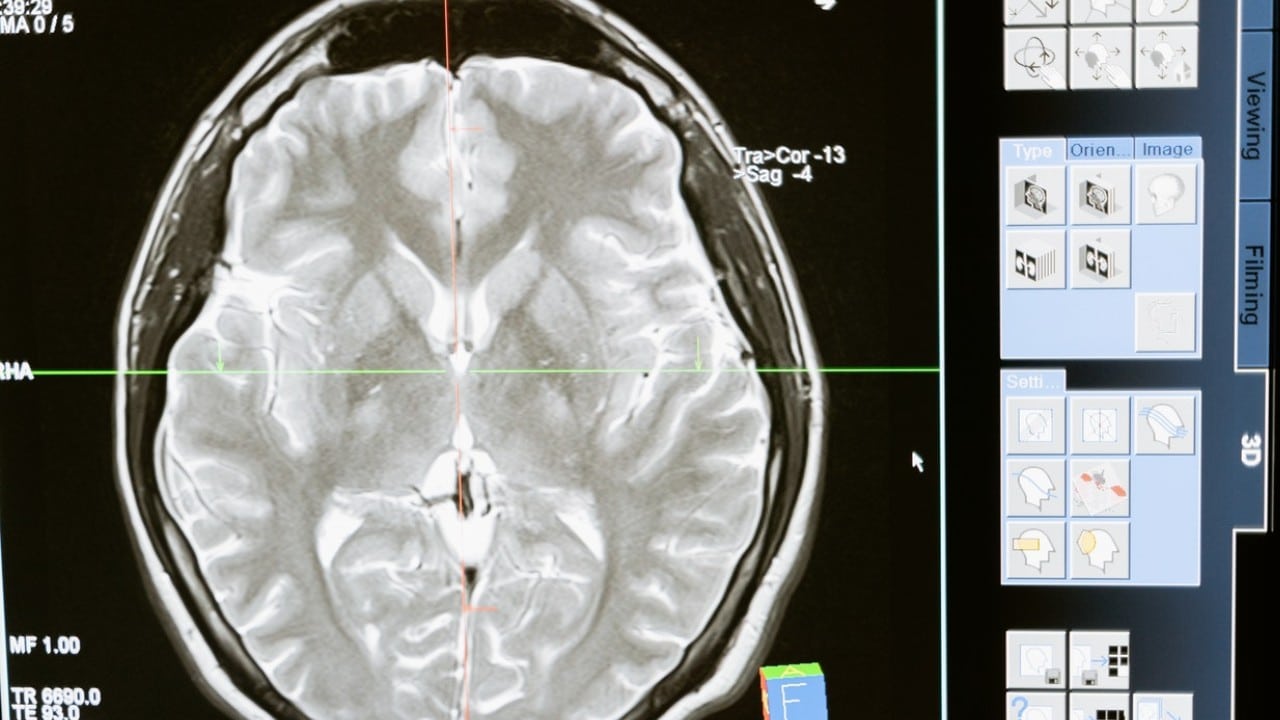

Un conjunto de síntomas, denominados como «niebla mental», es uno de los síntomas que más asusta a la comunidad médica y científica. Y es que es una de las principales secuelas neurológicas. En estudios de reciente publicación se encontró que había protección de células del sistema inmunitario y coágulos de sangre en el cerebro, pero no rastros del virus.

Las secuelas neurológicas también están presentes en el organismo | Fuente: Pexels